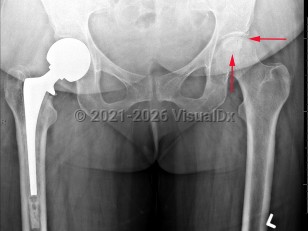

Imaging Studies image of Avascular necrosis of hip - imageId=7893859. Click to open in gallery.  caption: '<span>Serpiginous geographic  sclerosis with lucent center involving the subchondral portion of the  left femoral head compatible with AVN.</span>'

Serpiginous geographic sclerosis with lucent center involving the subchondral portion of the left femoral head compatible with AVN.